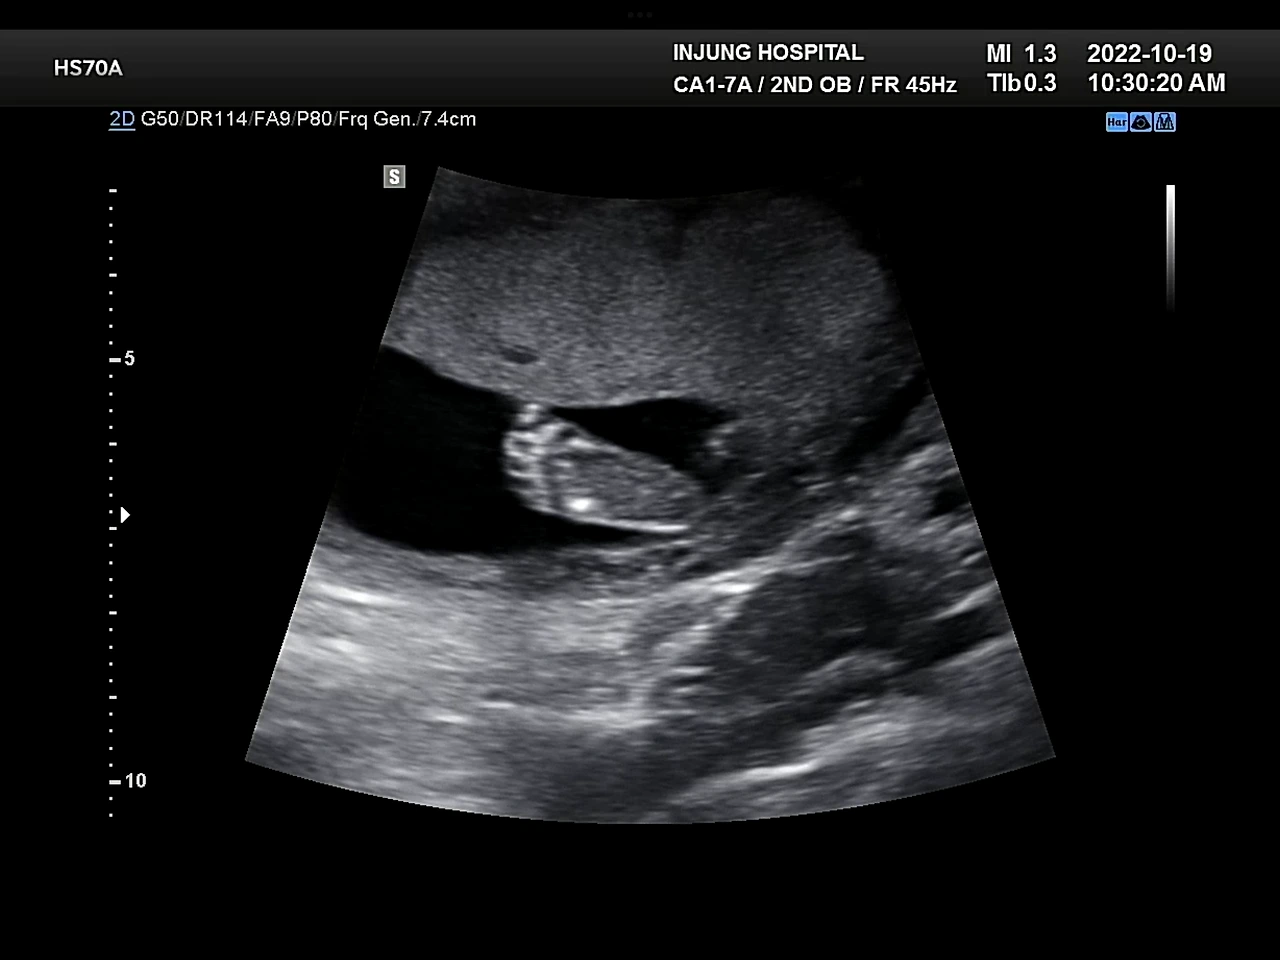

귀여운 옆모습, 귀여운 발꼬락

포도는 아들이었다. 의사 선생님이 초음파기계를 포도의 엉덩이 쪽에 갖다 대자 아들임을 알리는 그 무언가가 바로 보였다. 의사 선생님도 “따로 말 안 해줘도 아시겠죠?”라며 웃으셨다. 그게 너무 선명하게 보여서 나도 쌤이랑 같이 웃었다. 임신증상이나 입덧증상도 아인이랑 묘하게 달랐는데 그래서 그랬나 싶기도 했다. 암튼 우리 아들 안녕!